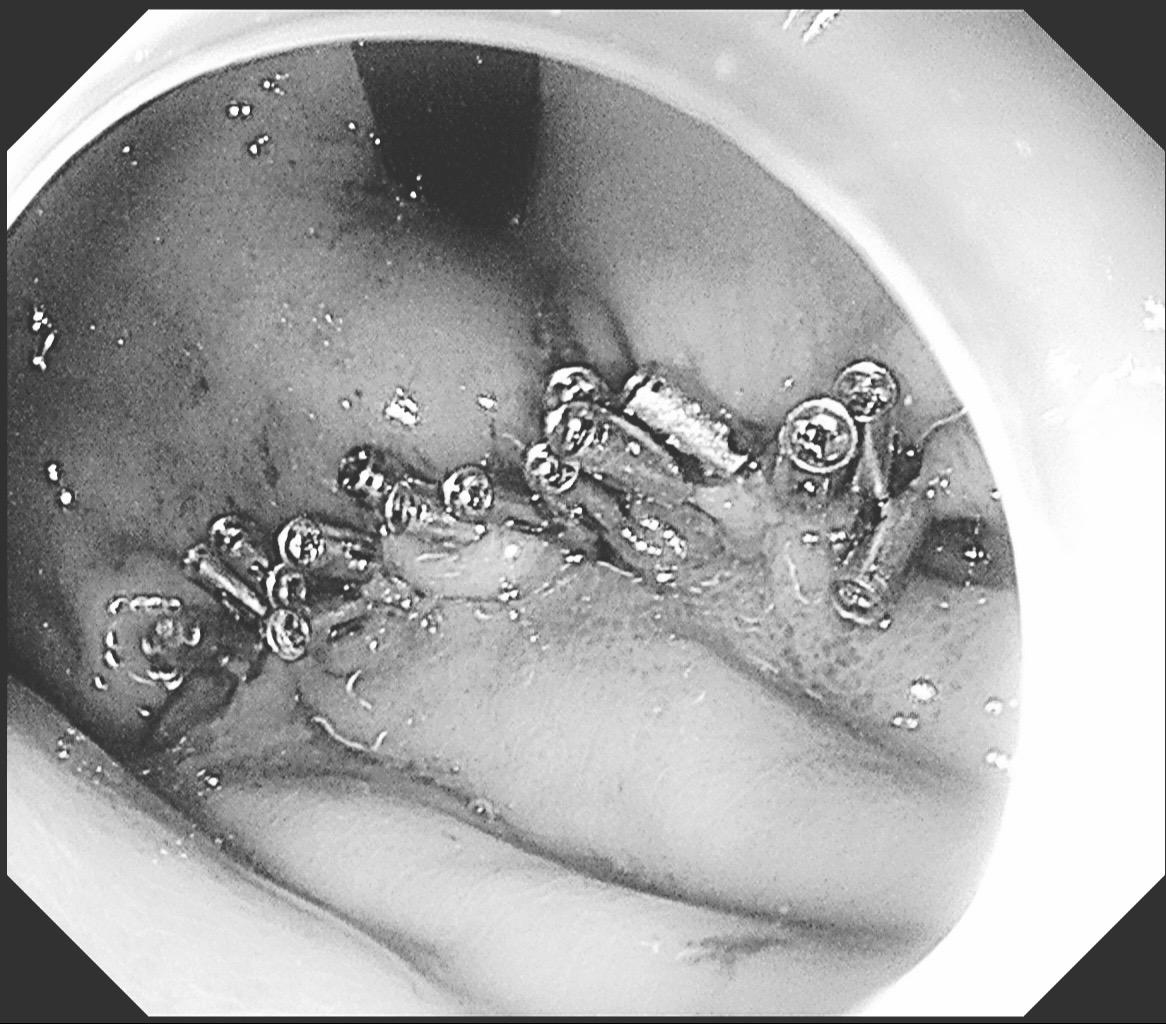

你性命相托,我必全力以赴。感谢信任!86岁,反复消化道出血1年多,血色素最低掉到6克。外科手术有可能保不住贲门,创伤大,家属拒绝。在外科老师备台、麻醉科的给力配合下,历时2个小时5厘米的瘤子完整切除并缝合。这种手术对患者是微创,对医生是巨创!